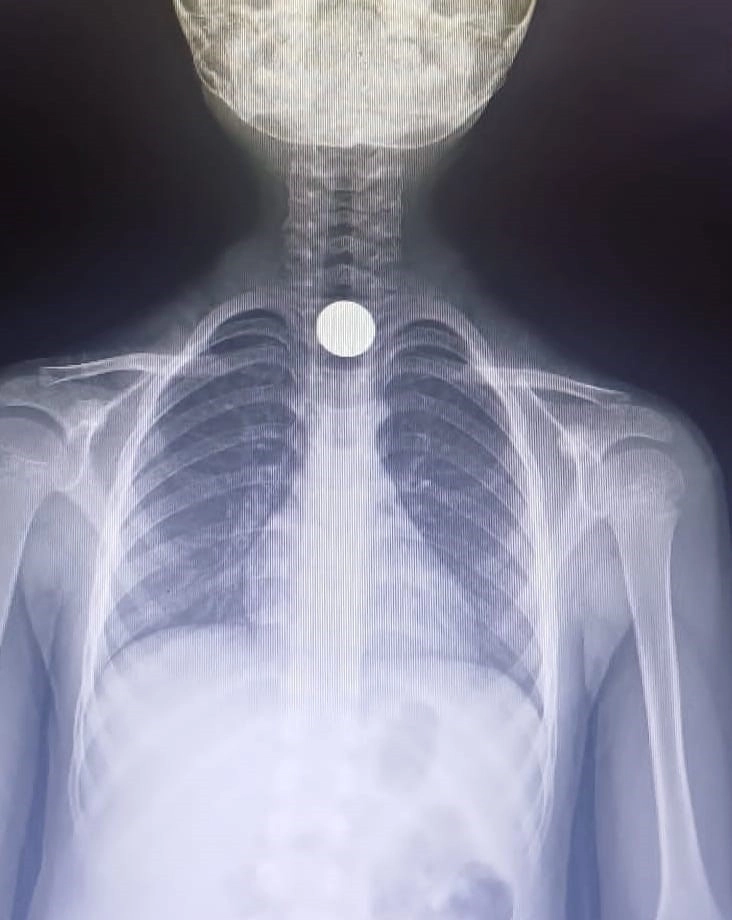

Bursa'nın İnegöl ilçesinde yerde bulduğu madeni parayı yutan 7 yaşındaki çocuk hastanede tedavi altına alındı. Baykoca Mahallesi'nde bulunan Mimar Sokak üzerindeki bir apartmanda gerçekleşti. Ahmet Eymen U. adındaki 7 yaşındaki çocuk, bulduğu 50 kuruşluk madeni parayı yutarak ailesini korkuttu. Durumu fark eden ailesi, hemen çocuğu özel bir araçla İnegöl Devlet Hastanesi'ne götürdü. Acil serviste yapılan ilk incelemeler sonucunda, paranın çocuğun yemek borusunda sıkıştığı belirlendi.

Bunun üzerine, Ahmet Eymen U., madeni paranın çıkarılması amacıyla Bursa'daki Yüksek İhtisas Eğitim ve Araştırma Hastanesine sevk edildi. İlgili olayın ardından polis, konuyla ilgili detaylı bir soruşturma başlattı.